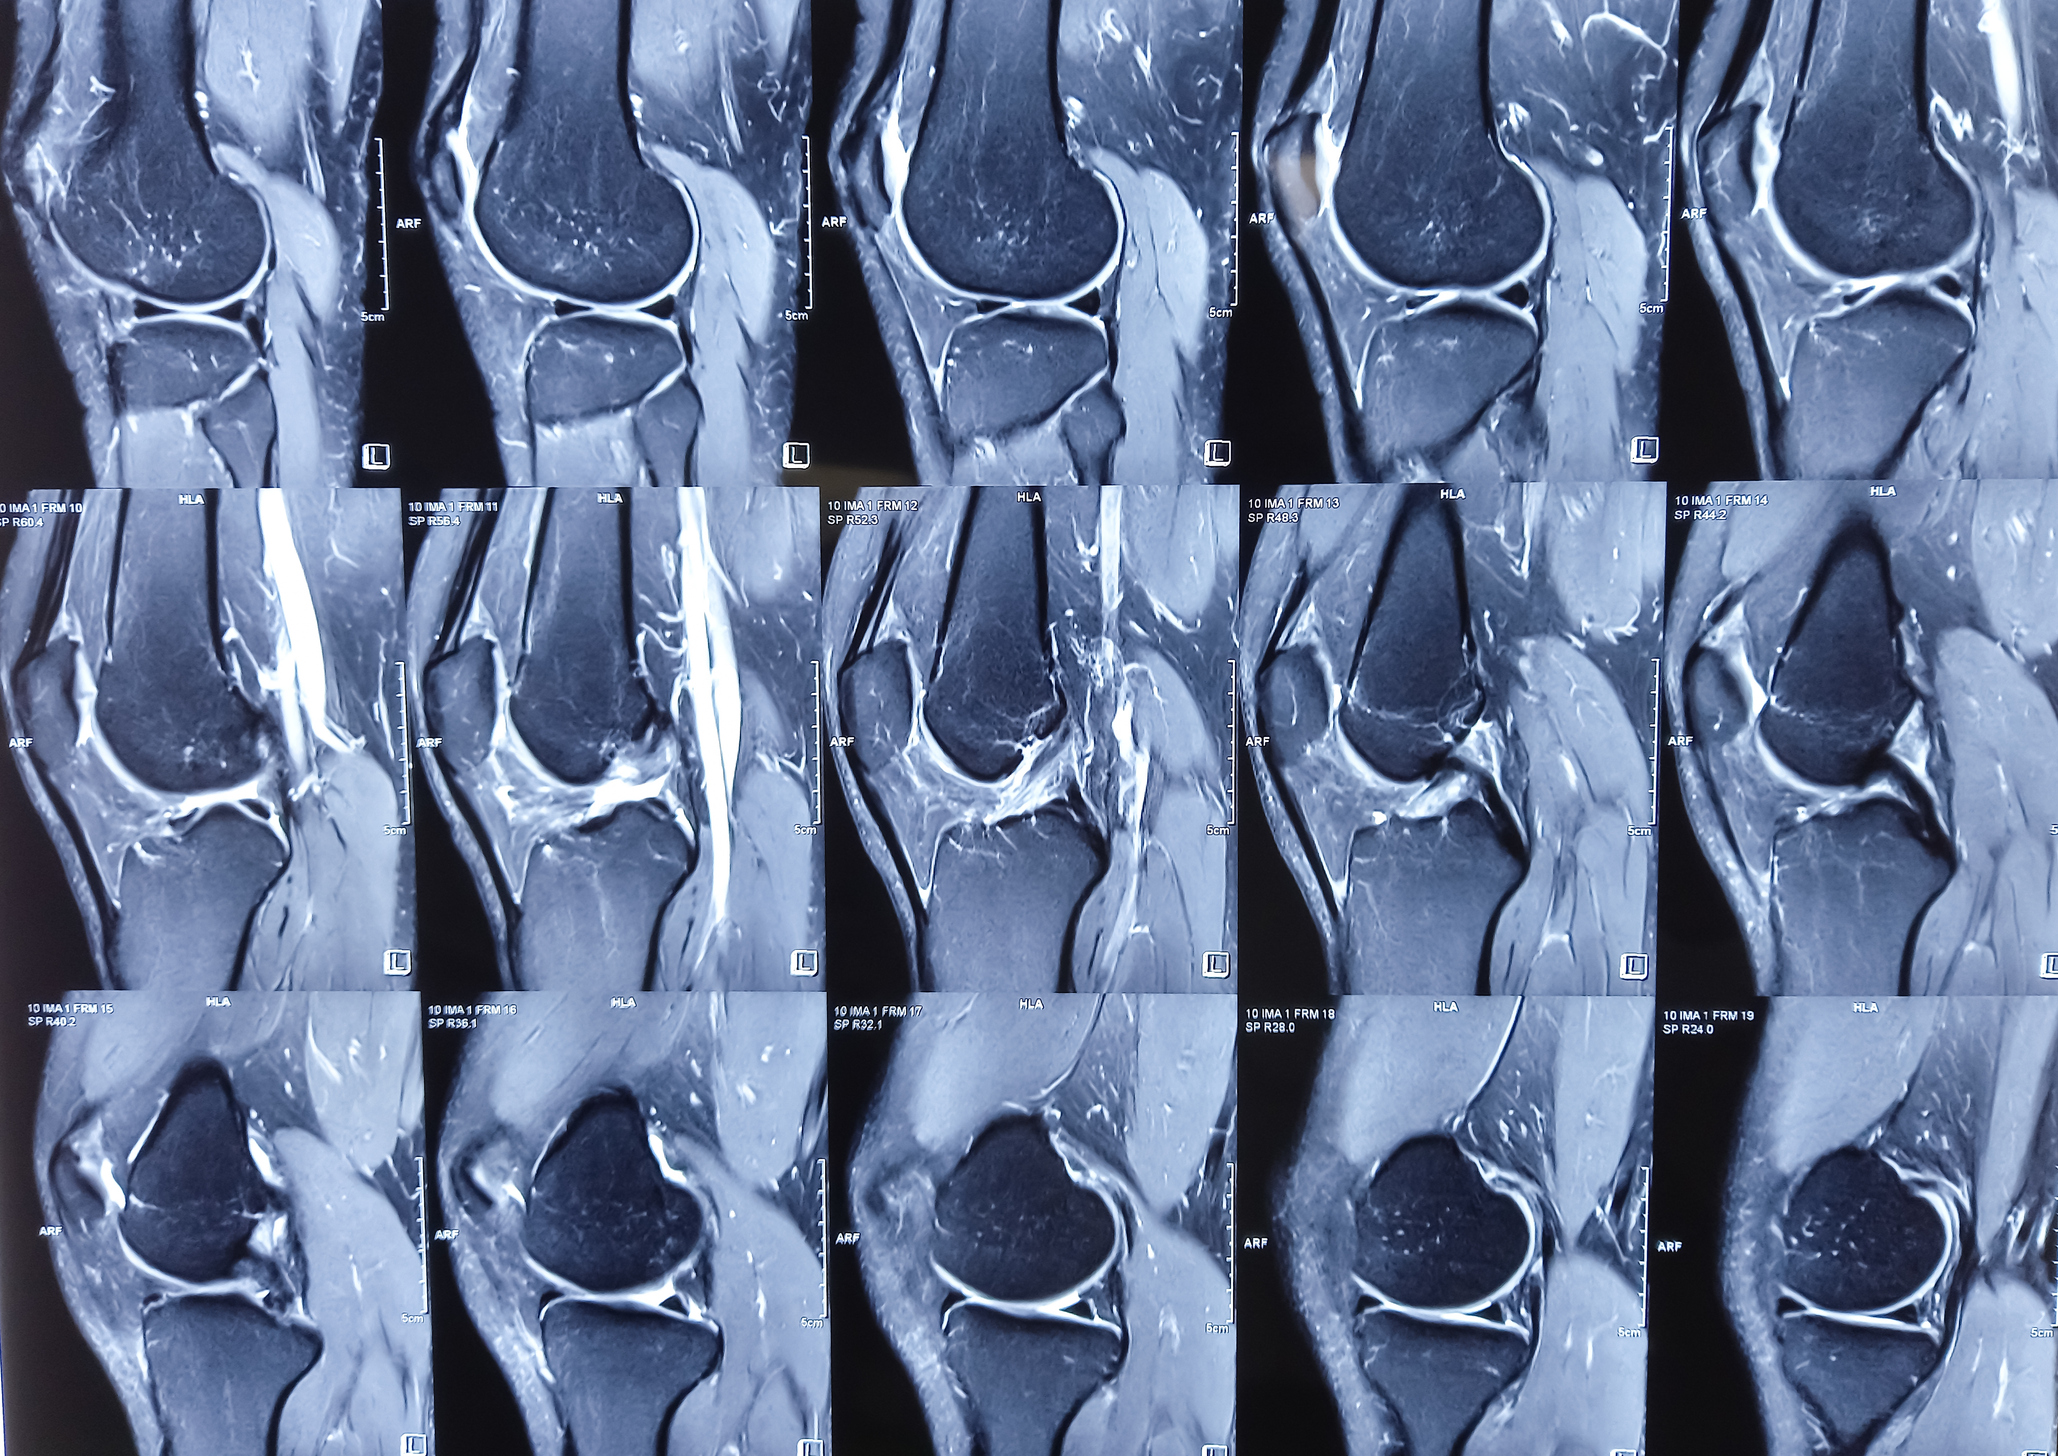

When symptoms of osteosarcoma are present, a full physical examination will be conducted, often in conjunction with an imaging test (x-ray, bone scan, MRI or PET). Any of these imaging tests will help determine whether the area in question is cancerous, and whether it might have started in, or spread to, another part of the body.